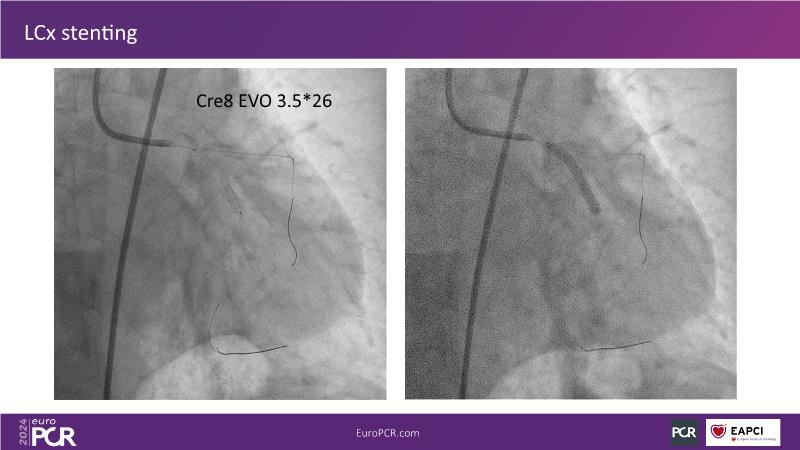

From innovation to reality: the impact of Cre8 EVO technology on complex PCI

Sponsored by Alvimedica